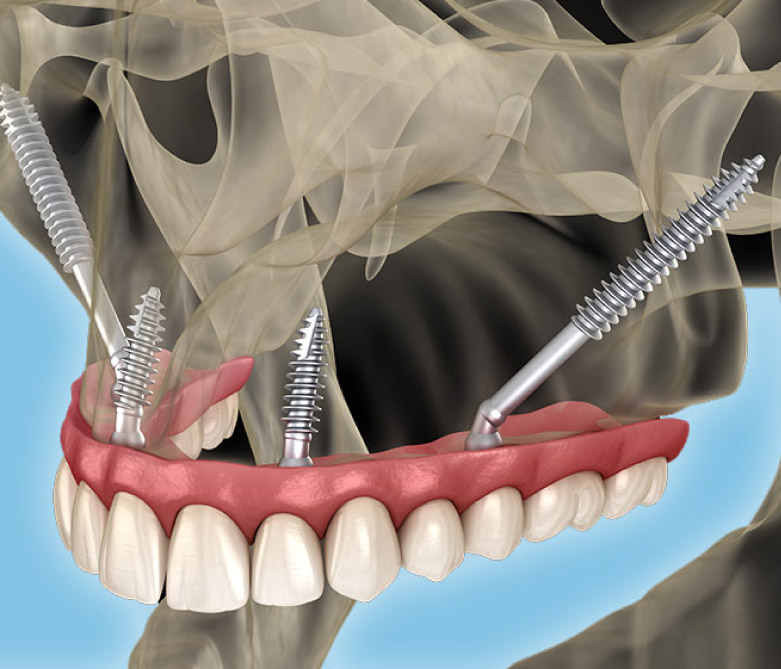

Zygomatic Implants

Anchored into the zygomatic bone (cheekbone) for patients with significant upper jaw bone loss.

Zygomatic Implants

Anchored into the zygomatic bone (cheekbone) for patients with significant upper jaw bone loss.